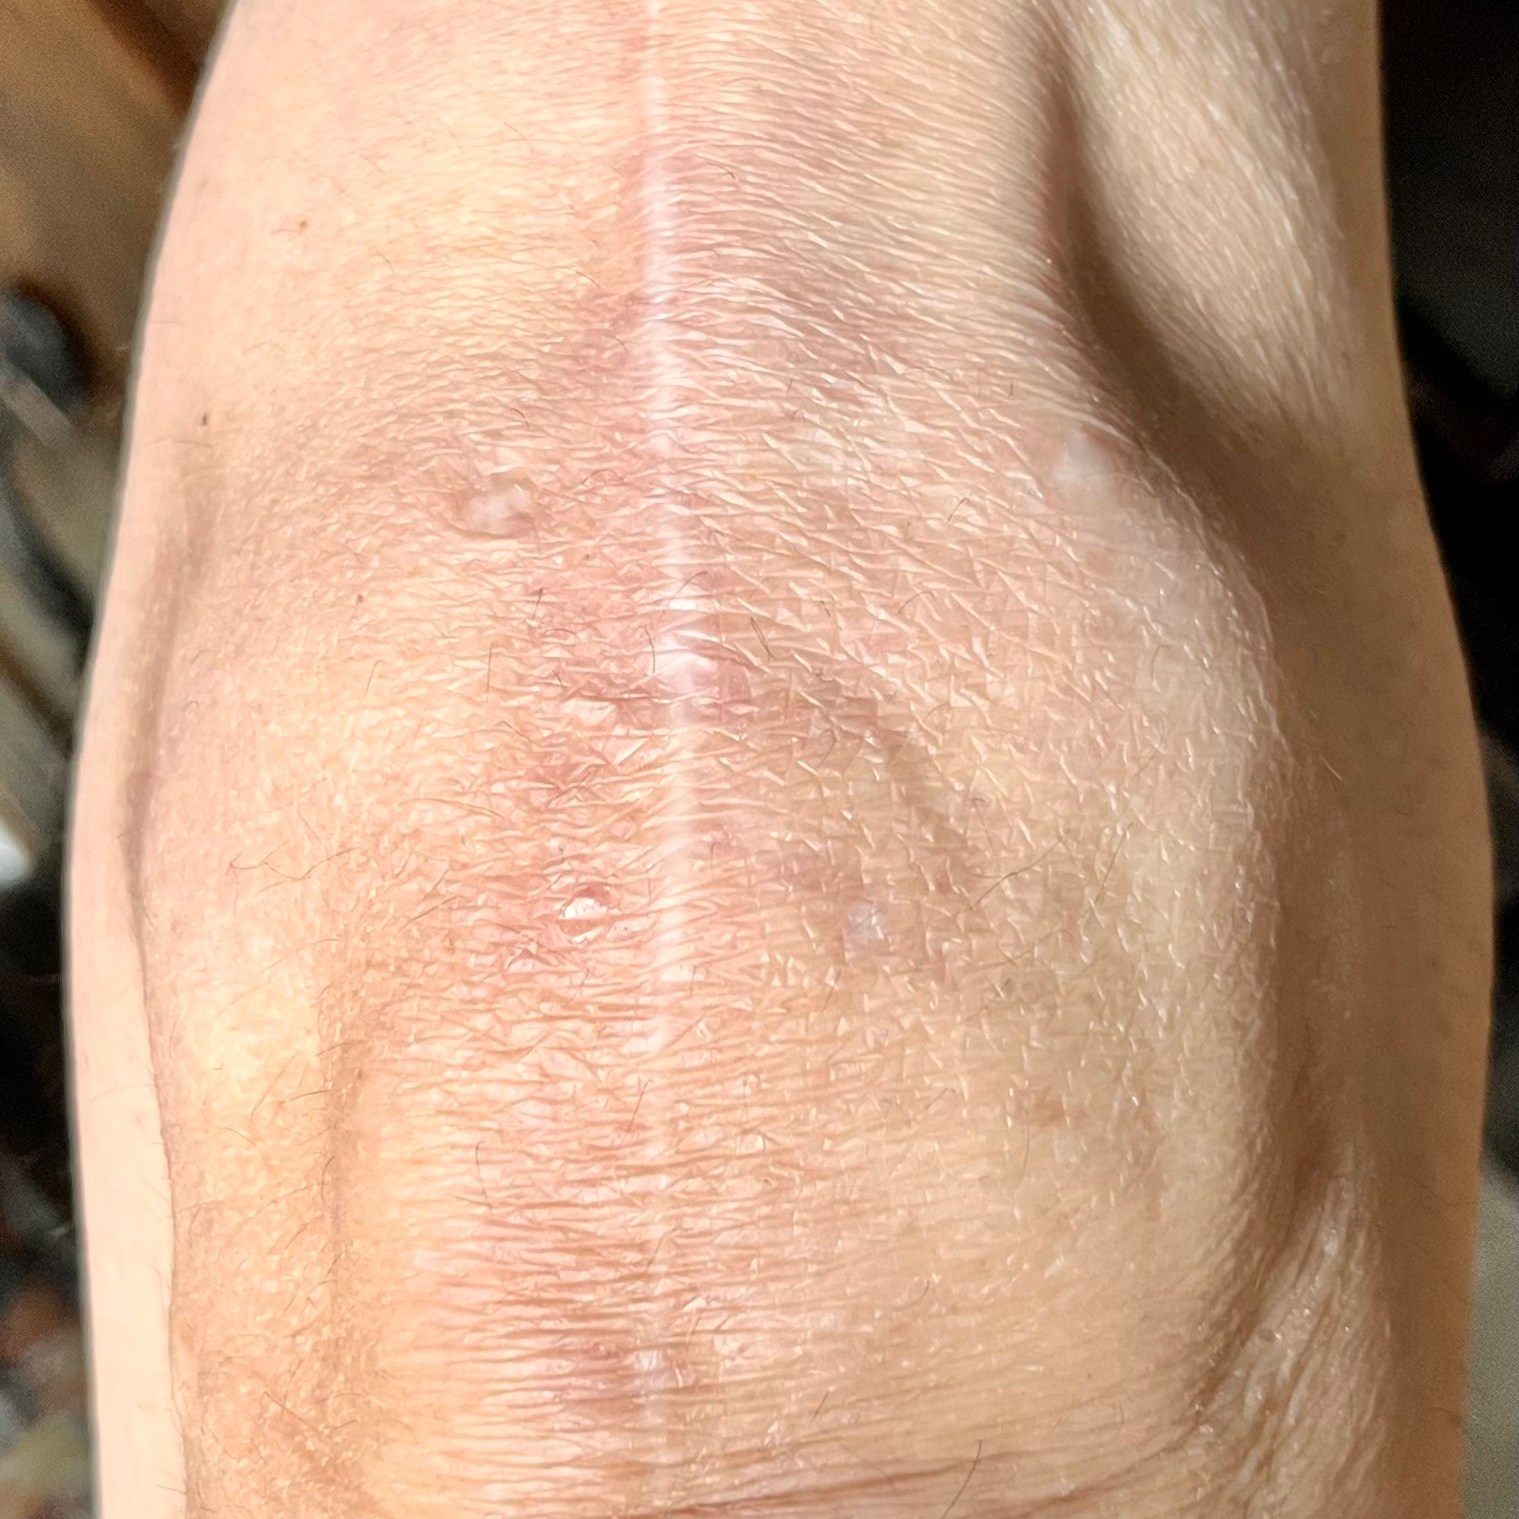

The operation went perfect. I had a nerve block so that my entire leg was pretty numb for the first 24 hours or so resulting in minimal pain. I stayed in the hospital one night and recuperated at home. The hospital sent a Physical Therapist to my home for the first week to teach me the various exercises to ensure my knee did not stiffen up. I did my exercises diligently and eventually made a full recovery with wonderful range of motion and almost no pain! Once the incision was fully closed, I applied my THC/CBD cream which helped with post-surgical pain and scar healing. Now, the incision is barely noticeable. I’m able to walk and do stairs without any pain now. However, after being active for a while, it starts to swell a bit and gets a little achy. Just my reminder to sit down and take it easy!